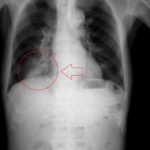

What We Can Learn About Coronavirus from Radiological Images of SARS and MERS?

A paper recently published in the American Journal of Roentgenology has found that scans of patients with COVID-19 share many similarities with imaging studies of severe...